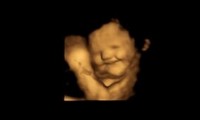

Giovedì, 22 Settembre 2022 09:35

Ricerca della Durham University: "Guardando le reazioni facciali dei feti possiamo presumere che una serie di stimoli chimici passi attraverso la dieta materna nell'ambiente fetale".